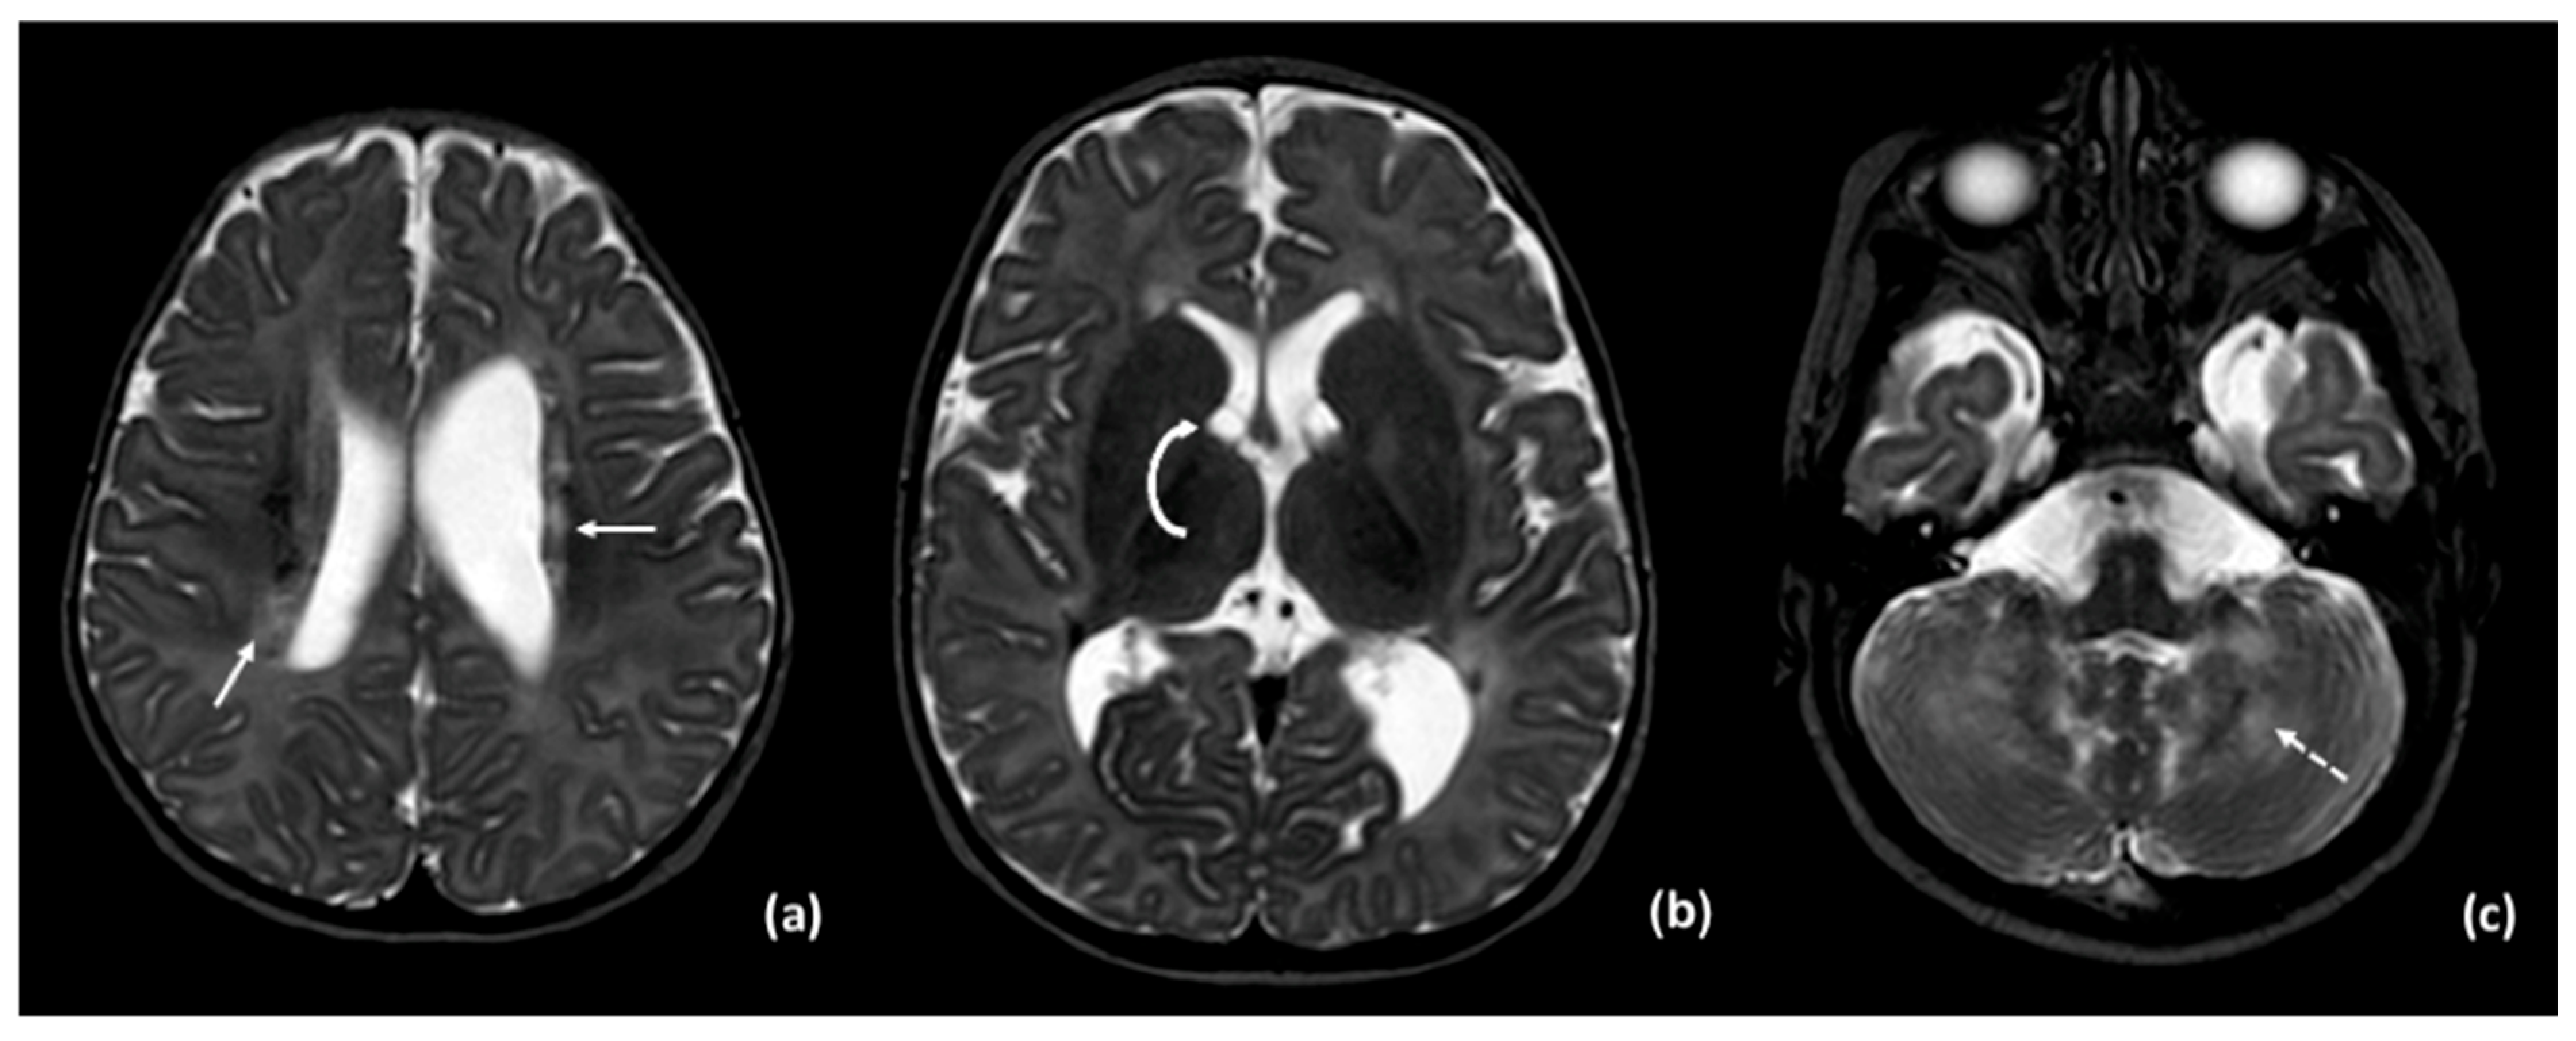

3.2. Results of Imaging Data